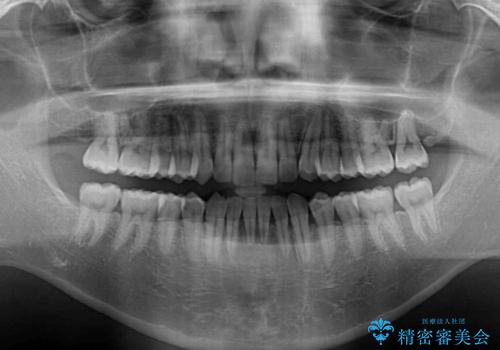

- 前歯のデコボコを気にして来院された患者様です。

インビザラインによるマウスピース矯正も適用となる歯列でしたが、できる限り自己管理の煩わしさのない状態で治したいとのことで、ワイヤー装置にて矯正治療を行うこととしました。

予定していた期間より長くかかりましたが、1年強できれいな歯列に仕上がりました。